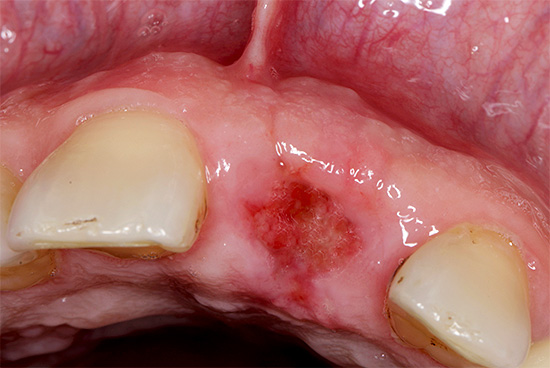

Se a cicatrização do tecido ocorrer sem problemas, um poço normal deve parecer algo como 1-2 em 1-2 dias: